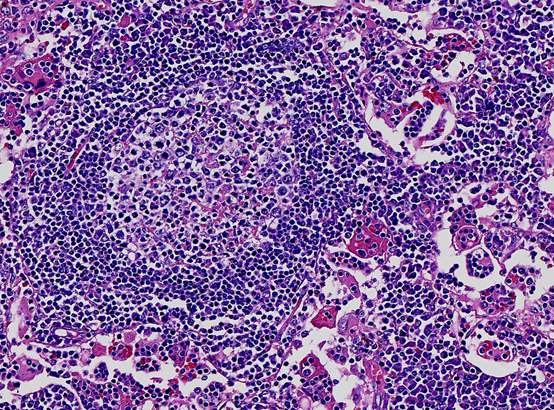

而事实上,它不过只是一个“淋巴组织增生”,本质上是一种慢性发炎,属于不治疗自己就可以好的小毛病。

人体淋巴增生是多么的“绚丽多彩”